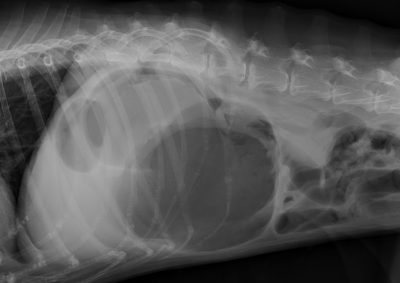

胃拡張捻転症候群(GDV)